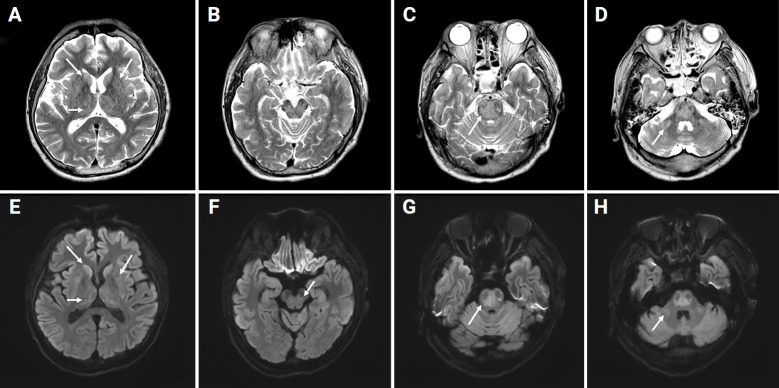

Osmotic demyelination syndrome (ODS) is an acute demyelinating disorder characterized by the loss of myelin in the center of the basis pons, defined as central pontine myelinolysis (CPM), and demyelination in locations outside the pons, defined as extrapontine myelinolysis (EPM). ODS including CPM and EPM is mainly caused by rapid correction of hyponatremia. However, there are several reports of ODS in medical conditions such as malnutrition; alcoholism; liver transplantation; malignancy; sepsis; and electrolyte imbalance including hypernatremia, hypokalemia, hypophosphatemia, and chronic illness. ODS caused by rapid correction of hyperammonemia or continuous hyperbilirubinemia without sodium fluctuations has rarely been reported. Because ODS may be irreversible, prevention is crucial. Herein, we report a case of ODS secondary to rapid correction of hyperammonemia and continuous hyperbilirubinemia.

Abstract Image